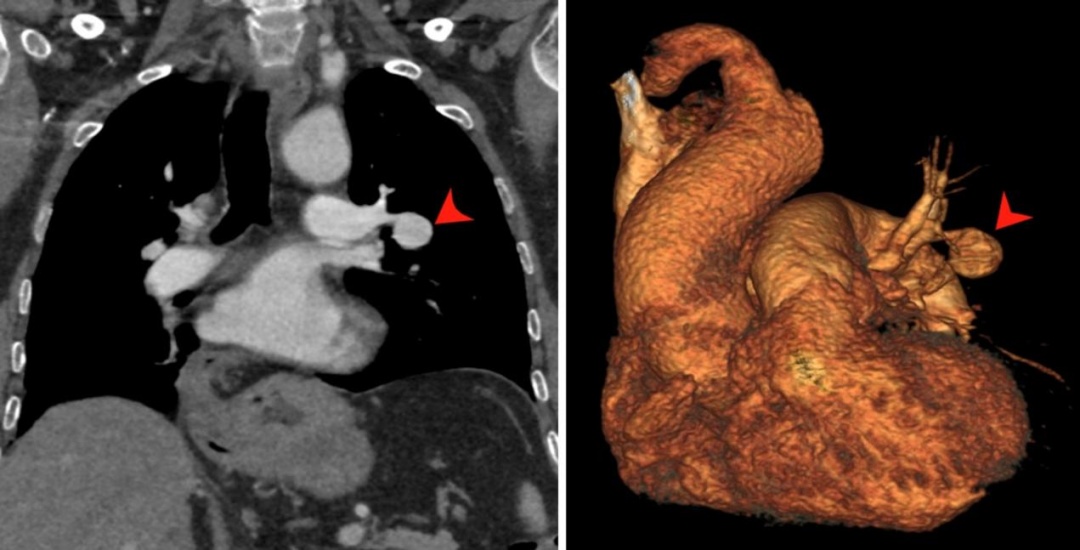

通过CT三维重建显示动脉瘤的位置及大小

随后,王庆兵为沈老伯进行了介入治疗。“通过栓塞肺动脉瘤所在的血管,有效地阻止血液流入瘤体,沈老伯的病情得到了有效控制,全程仅仅花了半小时。”王庆兵介绍,介入治疗是目前治疗肺动脉瘤的主要方式之一,它通过导管等器械进入患者体内,可以精确地定位和治疗肺动脉瘤,避免开放手术可能带来的较大创伤。术后,沈老伯恢复良好,已康复出院。